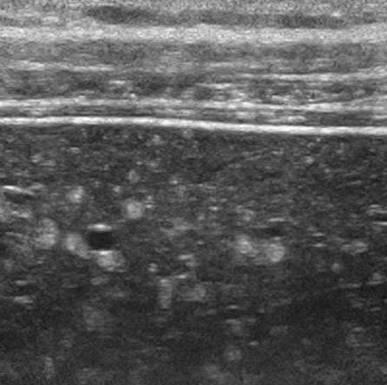

Hamartoma đường mật

» Thông tin: Nam giới – 34 tuổi.

» Lâm sàng: Kiểm tra sức khỏe.